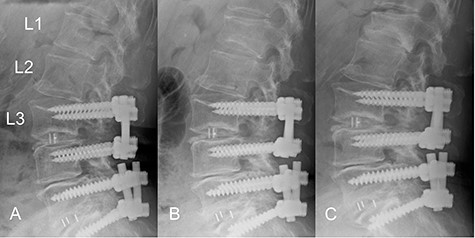

The patient was an 82-year-old Japanese woman who had presented 2 months earlier with pain and numbness in her left lower extremity. She had a history of vertebral fracture at L1 4 months previously for which she had been treated with a lumbar orthosis for 2 months (Fig. 1). Magnetic resonance imaging of the lumbar spine demonstrated foraminal stenosis at the L2–L3 level (Fig. 2A). CT images of the lumbar spine revealed ossification in the capsular portion of the ligamentum flavum around the L2–L3 facet joint (Fig. 2B–D). She underwent L2–L3 foraminotomy with excision of the capsular portion of the OLF. The patient’s symptoms disappeared immediately after surgery. Postoperative CT scans showed good decompression at the operated level (Fig. 2E and F).

Time course of a vertebral fracture at L1. (A) Radiographic image obtained just before the vertebral fracture occurred. (B) The vertebral fracture had occurred at L1 4 months before surgery. (C) Radiographic image obtained when the patient presented with symptoms of radiculopathy shows no apparent posterior slip of the L2 vertebra. The L1 vertebral body was deformed into a wedge shape.